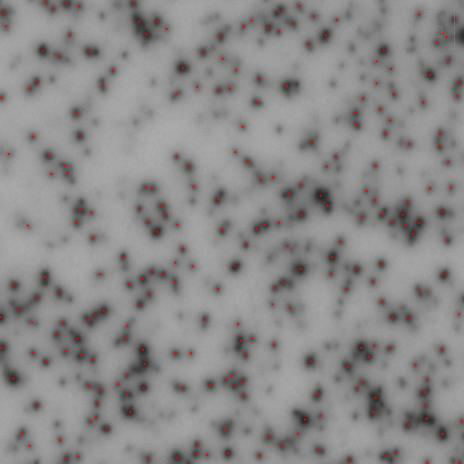

精確斑點定位

基于RAWSpot技術的精準定位,可以準確獲得斑點位置及對應細胞的分泌類型。

ELISpot斑點中心定位